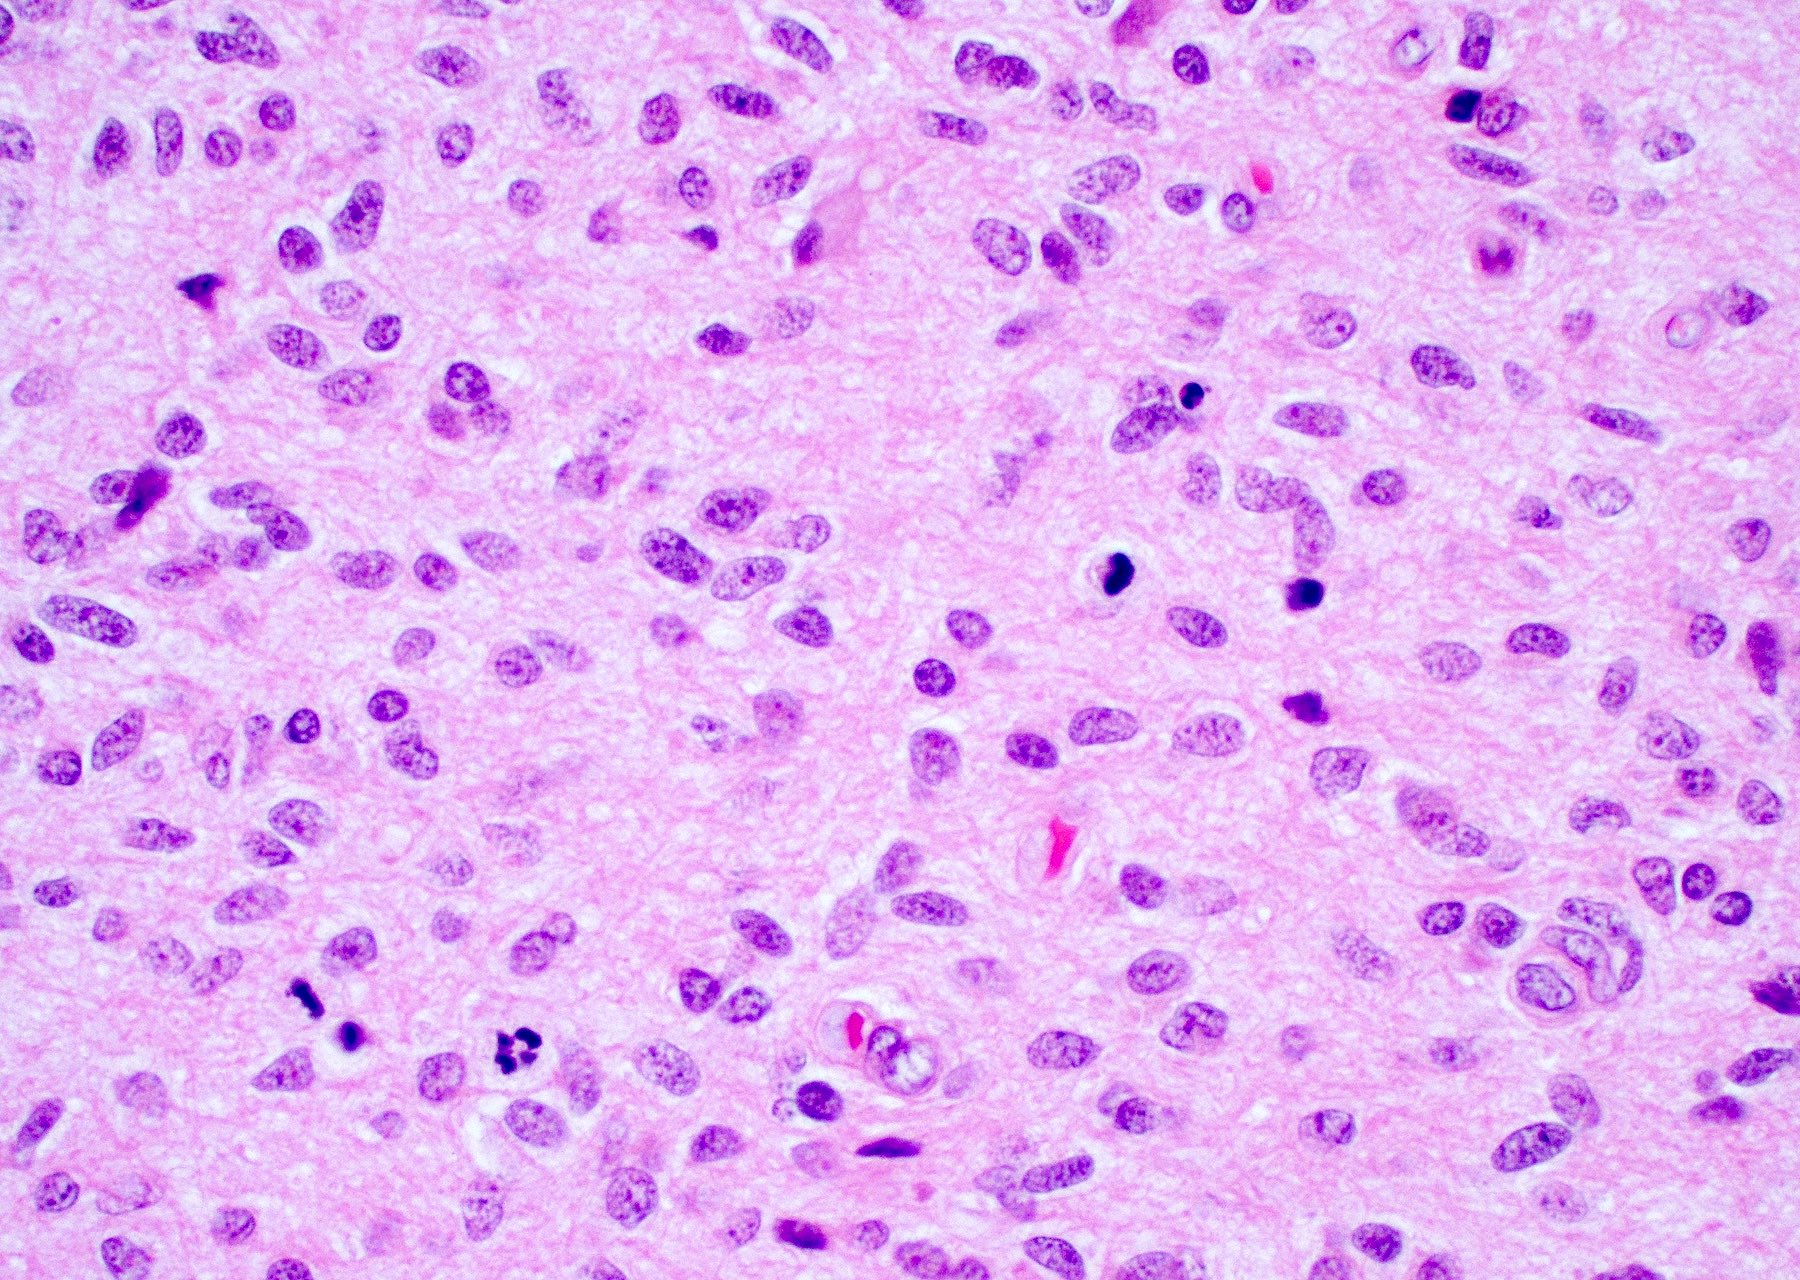

Microscopic (histologic) description

- Infiltrating, hypercellular astrocytic neoplasm often with hyperchromatic, elongated nuclei and irregular nuclear membranes

- Typically mitotically active, though not required if molecular criteria are met

- Microvascular proliferation or necrosis is required for a histologic diagnosis of GBM

- Microvascular proliferation: multilayered, small caliber vessels with glomeruloid appearance (J Neuropathol Exp Neurol 1992;51:488)

- Necrosis: can be geographic or pseudopalisading with neoplastic cells surrounding central necrosis

- Greater association of thrombosis and necrosis in IDH wild type GBM than in IDH mutant grade 4 astrocytomas (Acta Neuropathol 2016;132:917)

- Variable cell morphology: undifferentiated / primitive neuronal cells, astrocytic, gemistocytic, oligodendroglial-like, small cell, lipidized, granular, epithelioid, giant cells, mesenchymal metaplasia and epithelial metaplasia

- Small cell change: monomorphic cells with small, round or angulated, hyperchromatic nuclei and brisk mitotic activity

- Associated with EGFR amplification (Clin Neuropathol 2005;24:163, J Neuropathol Exp Neurol 2001;60:1099)

Microscopic (histologic) images

Contributed by Bharat Ramlal, M.D. and Meaghan Morris, M.D., Ph.D.